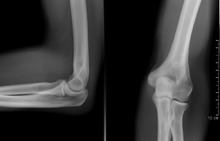

A plain radiograph of the elbow